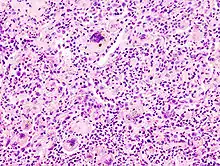

LANGHANS-Riesenzellen in einem Tbc-Granulom, transbronchiale Biopsie

Fremdkörper-Riesenzellen bei Aspirationspneumonie, Autopsiepräparat, H&E.